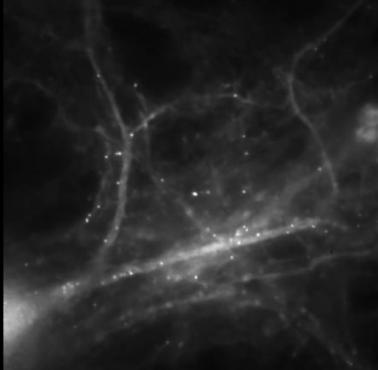

Układ nerwowy człowieka. Na zdjęciu widać m.in. mózg, rdzeń kręgowy, nerwy rdzeniowe i splot lędźwiowy